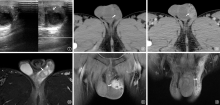

男性生殖系统结核(male genital tuberculosis,MGTB)可发生在男性生殖系统的各个器官,MGTB临床症状不典型或无临床症状,容易造成漏诊和误诊,随着医学影像学技术的发展,影像学表现在MGTB的诊断和鉴别诊断中有着重要的作用。作者旨在系统归纳男性生殖系统各个器官结核的超声、计算机断层扫描(computed tomography,CT)和磁共振成像(magnetic resonance imaging,MRI)的表现,提高对MGTB的认识和临床诊断能力。

| [27] | 程洁, 邱小伟, 尤四峰, 等. CT及MRI对附睾结核诊断的特征性分析. 实用放射学杂志, 2023, 39(4):615-617, 638. doi:10.3969/j.issn.1002-1671.2023.04.024. |

| [28] | Man J, Cao L, Dong Z, et al. Diagnosis and treatment of epididymal tuberculosis: a review of 47 cases. PeerJ, 2020, 8:e8291. doi:10.7717/peerj.8291. |

| [29] |

Yang B, Zhou R, Wang X, et al. Magnetic resonance imaging features of epididymal and/or testicular tuberculosis: a case series. BMC Med Imaging, 2025, 25(1):157. doi:10.1186/s12880-025-01699-w.

URL pmid: 40355825 |

| [30] | Jung YY, Kim JK, Cho K. Genitourinary tuberculosis: comprehensive cross-sectional imaging. AJR Am J Roentgenol, 2005, 184(1):143-150. doi:10.2214/ajr.184.1.01840143. |

| [31] | Michaelides M, Sotiriadis C, Konstantinou D, et al. Tuberculous orchitis US and MRI findings. Correlation with histopathological findings. Hippokratia, 2010, 14(4):297-299. |